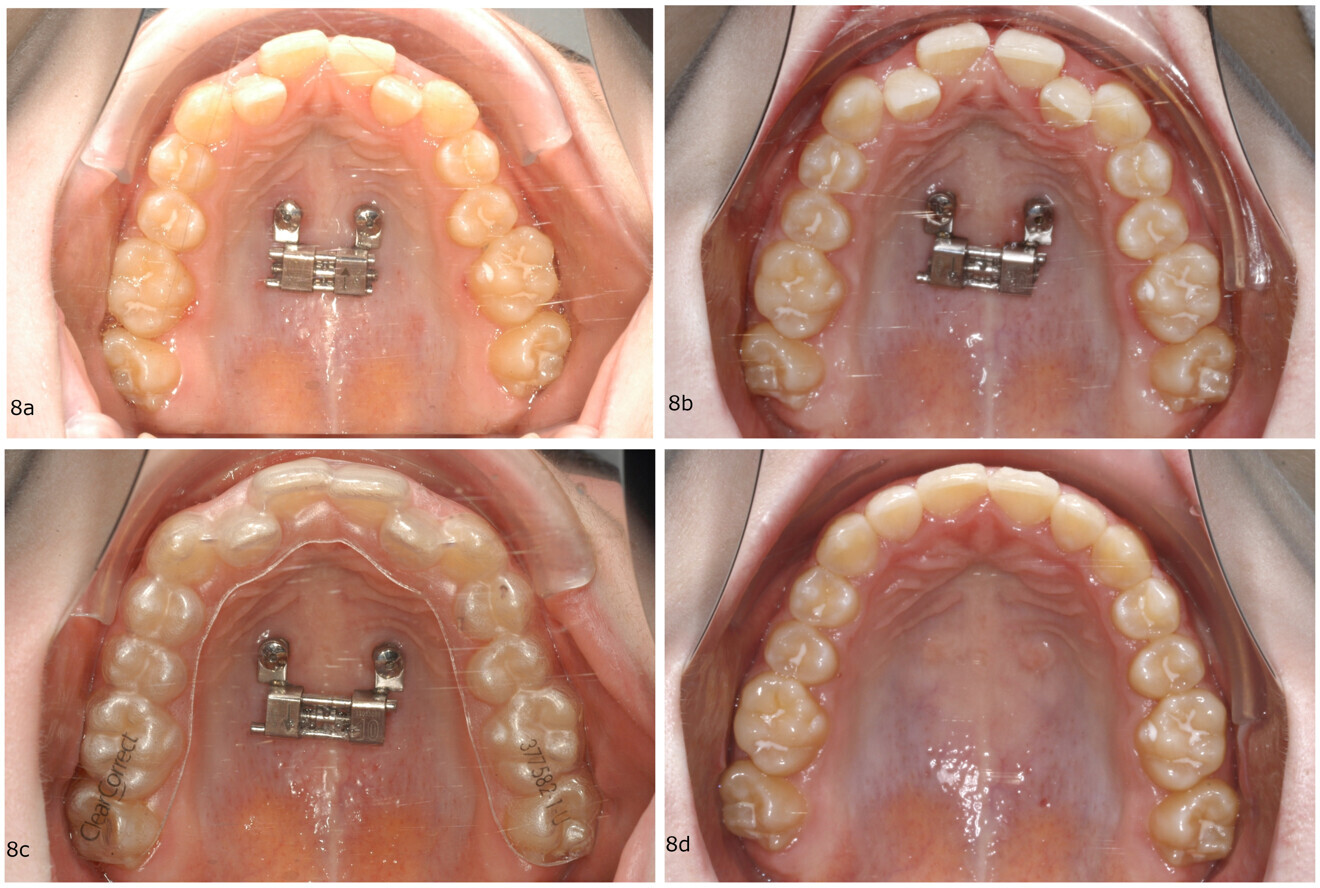

Figs. 6a–d: Treatment progress of a 25-year-old female patient with anterior crowding and incisor proclination. (a) Beneslider in place. (b) Situation after molar distalisation. (c) Subsequent aligner finishing. (d) Result.

Clinical case (Beneslider)

A 25-year-old female patient presented with maxillary anterior proclination, anterior crowding and an Angle Class II malocclusion. The maxillary posterior teeth were noted to be mesially positioned. The patient specifically requested an invisible orthodontic treatment option, to be performed on a non-extraction basis.

The treatment plan was bilateral distalisation with the Beneslider and finishing with aligners. After insertion of a Beneslider (Fig. 6a; PSM) and distalisation of the molars (Fig. 6b), digital scans were taken for fabrication of aligners (Fig. 6c; Invisalign). As soon as the molars had been moved into a Class I occlusion, all the spaces were closed distally using the aligners. The treatment was completed after 15 months (Fig. 6d).